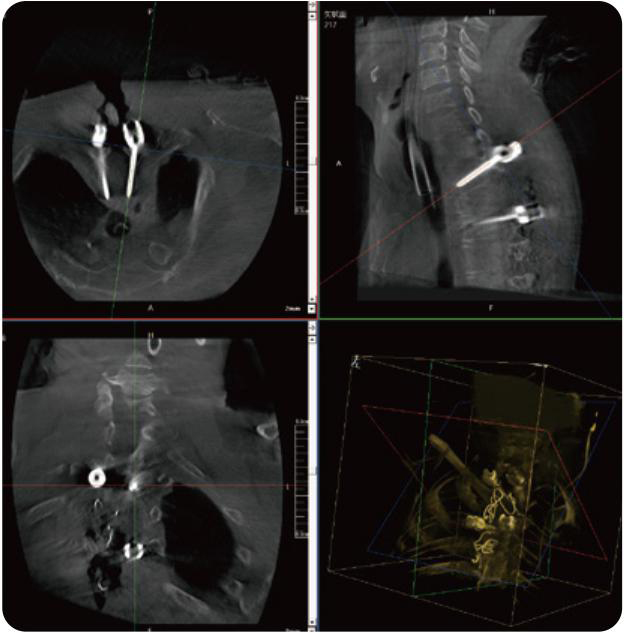

Clinical picture

临床图片